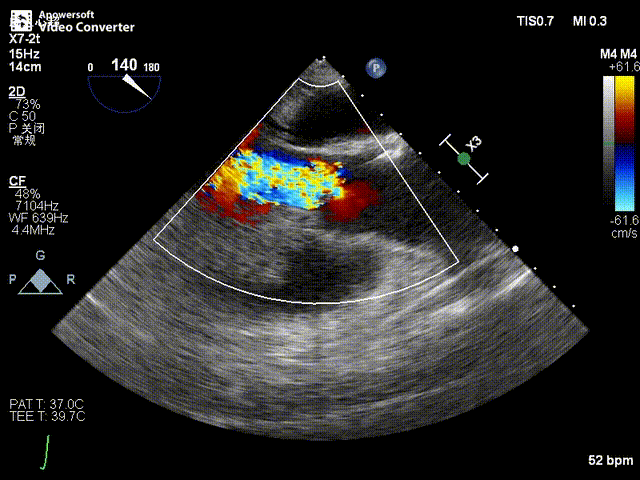

术后超声影像图

患者全麻后,于左侧心尖3-4cm处进行微创手术切口。在DSA及超声引导下,输送Ken-Valve瓣膜系统进入左心室,边调弯边推送,使得瓣膜在术中始终保持较好的同轴性,从送入输送器到瓣膜释放不足十分钟。术后即刻患者返流消失,于外科杂交手术室拔除气管插管,次日即由ICU转入普通病房。

张海波教授:此病例为单纯的主动脉瓣关闭不全患者。CT分析提示,主动脉根部角度为78°,为重度“横位心”患者,给瓣膜的植入带来了巨大的挑战。术中采用了Ken-Valve输送系统,进入左心室后进行调弯,减少了对升主动脉的影响,从而增加了瓣环上的操作空间,了瓣膜的同轴性,整个手术过程十分顺畅。对于重度横位心、单纯主动脉瓣关闭不全的病例,这是难能可贵的。术后即刻患者返流消失,结果令人满意。由于Ken-Valve瓣膜具有独特的定位件及裙边设计,其他长支架自展瓣难以企及。